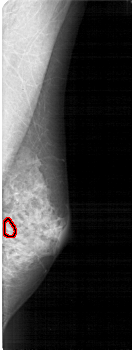

A_1867_1.RIGHT_MLO

RIGHT_MLO LINES 5236 PIXELS_PER_LINE 1966 BITS_PER_PIXEL 12 RESOLUTION 43.5 OVERLAY

FILE: A_1867_1.RIGHT_MLO.OVERLAY

TOTAL_ABNORMALITIES 1

ABNORMALITY 1

LESION_TYPE CALCIFICATION TYPE PLEOMORPHIC DISTRIBUTION CLUSTERED

ASSESSMENT 4

SUBTLETY 2

PATHOLOGY BENIGN

TOTAL_OUTLINES 1

BOUNDARY